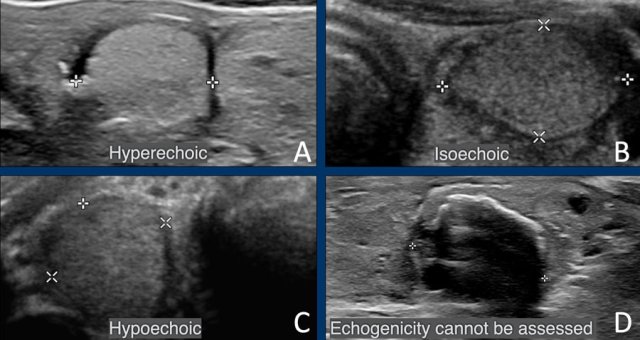

Echogenicity

Hyperechoic and isoechoic lesions  both get 1 point, so for the score it does not matter.

The echogenicity is compared with normal thyroid parenchyma

Hypoechoic means that a lesion is more hypoechoic than normal thyroid parenchyma.

If the echogenicity cannot be assed, for example because of calcifications, 1 point is given for the echogenicity.